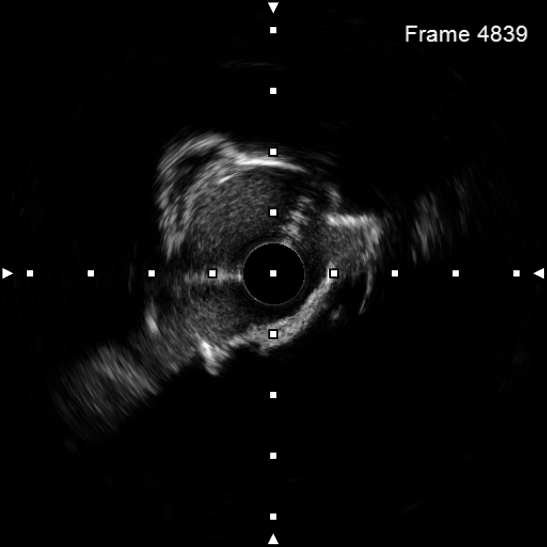

该患者入院后,完善相关检查并再次建议行CABG治疗,但家属仍拒绝,遂考虑再次行PCI手术干预。冠脉造影提示患者冠脉右冠状动脉中段70-95%再狭窄,左主干末端80%狭窄,前降支原支架中远段 80-95%再狭窄,回旋支完全闭塞,急需手术尽快解决冠脉血流灌注问题,否则随时有生命风险,但患者多处支架内/节段内再狭窄,造影提示钙化明显,外院已尝试无法扩张,经手术团队充分讨论后,计划在IABP支持下,先进行右冠状动脉干预,利用IVUS精准评估原支架再狭窄部位情况,采用旋磨或Shockwave冲击波球囊处理无法扩张的病变部位,右冠处理后择期进行左冠状动脉干预。在制定了详尽的手术计划后,手术团队首先对患者的右冠状动脉行IVUS检查,结果提示该患者右冠中段支架局部膨胀不良,局部支架面积6.67mm²,管腔内多处可见钙化小结及270°以上钙化,IVUS钙化积分达3分。由于膨胀不良处原支架后方可见钙化斑块,常规旋磨效果不佳,对于此类钙化病变,IVL处理是最佳方案。手术团队对近端采取棘突球囊及高压球囊进行扩张,采用Guidezilla辅助下输送3.0mmx12mm Shockwave冲击波球囊于右冠钙化处进行冲击波钙化斑块碎裂术,通过IVUS证实支架内的新生钙化病变得到松解,原膨胀不良部位支架面积达到7.76mm²,后经过高压球囊充分预处理,顺利完成右冠支架植入,术后复查右冠原膨胀不良部位支架面积9.17mm²。

图3 IVUS示右冠中段支架膨胀不良,支架内多处可见新生钙化病变